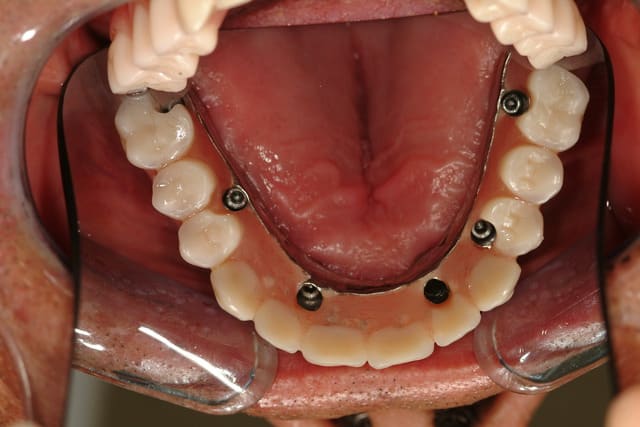

Voici déjà un cas avec 6 implants maxillaire et mandibulaire.

Le bas est pour le moment en résine, on doit passer plus tard à un bridge vissé sur armature métallique.

Le maxillaire a été fait en 2009 et la mandibule en 2007.